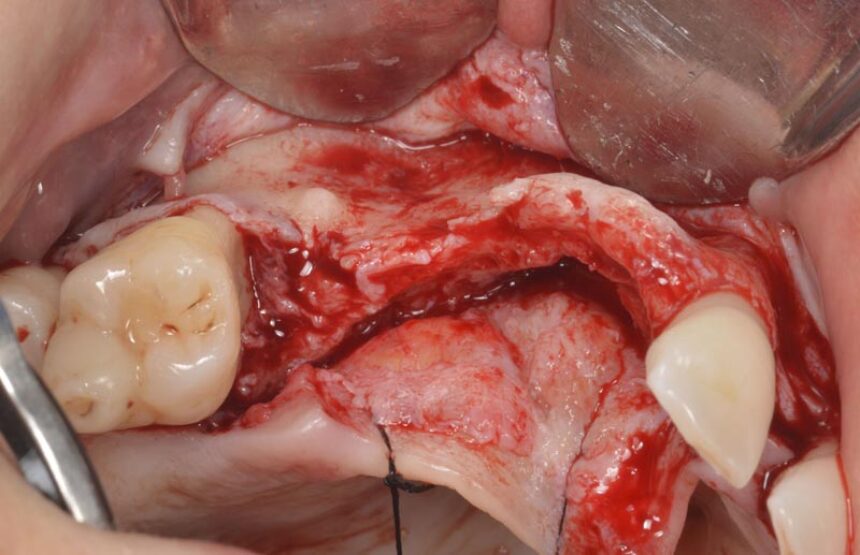

Πιο συγκεκριμένα, ο Prof. Massimo Simion, είναι ένας από τους πρωτεργάτες της διαδικασίας της Κατευθυνόμενης Οστικής Αναγέννησης στο χώρο της εμφυτευματολογίας. Μέσα από την τριαντακοετή εμπειρία του θα μας μεταφέρει τις εμπειρίες του στο χώρο αυτό καθώς και τα μυστικά επιτυχίας σε περιστατικά εκτενούς έλλειψης της φατνιακής ακρολοφίας τόσο στην άνω, όσο και στην κάτω γνάθο, αλλά και θα παρουσιάσει την αντιμετώπιση διαφόρων επιπλοκών που μπορεί να προκύψουν στην αντιμετώπιση αυτών των περιστατικών που αποτελούν πρόκληση για τους κλινικούς.

Κατηγοριοποίηση ατροφικού οστού των γνάθων – Σχεδιασμός θεραπείας και χειρουργικές ενδείξεις. Η πλήρως νωδή άνω γνάθος: διάφορες ατροφίες και αντίστοιχες χειρουργικές τεχνικές – Βίντεο με οστικά μοσχεύματα και Καθοδηγούμενη Οστική Ανάπλαση (GBR).

Η πλήρως νωδή κάτω γνάθος: διάφορες ατροφίες και αντίστοιχες χειρουργικές τεχνικές – Κοντά εμφυτεύματα - Οστικά μοσχεύματα – GBR

Οριζόντια και Κάθετη Αύξηση της Ακρολοφίας: χειρουργικό υπόβαθρο - χειρουργικές τεχνικές – απορροφήσιμες και μη-απορροφήσιμες μεμβράνες – λήψη οστικού μοσχεύματος από ενδο-στοματικά σημεία – βίντεο

Μακροπρόθεσμα αποτελέσματα μετά από 30 χρόνια εμπειρίας.

Αντιμετώπιση επιπλοκών της GBR.

Διάγνωση, πρόληψη και αντιμετώπιση της περι-εμφυτευματίτιδας